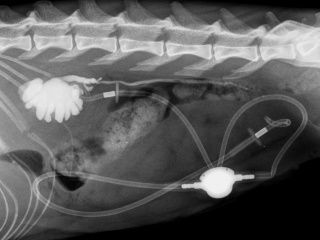

Du produit de contraste peut être injecté dans les voies urinaires (urétro-cystographie rétrograde, cystographie à double contraste, pyélographie antégrade) ou dans le colon (colonographie) pendant l’examen radiographique. Cela permet de détecter des obstructions urétrales, urétérales, ou des anomalies du colon.

Certaines pathologies chirurgicales comme les obstructions gastro-intestinales dues à l'ingestion d'un corps étranger, les torsions spléniques, ou les calculs urinaires peuvent facilement être diagnostiquées à l'échographie.

L’échographie est la technique de choix pour effectuer les suivis de SUB (« subcutaneous ureteral bypass ») en cas d’obstruction de l’uretère.